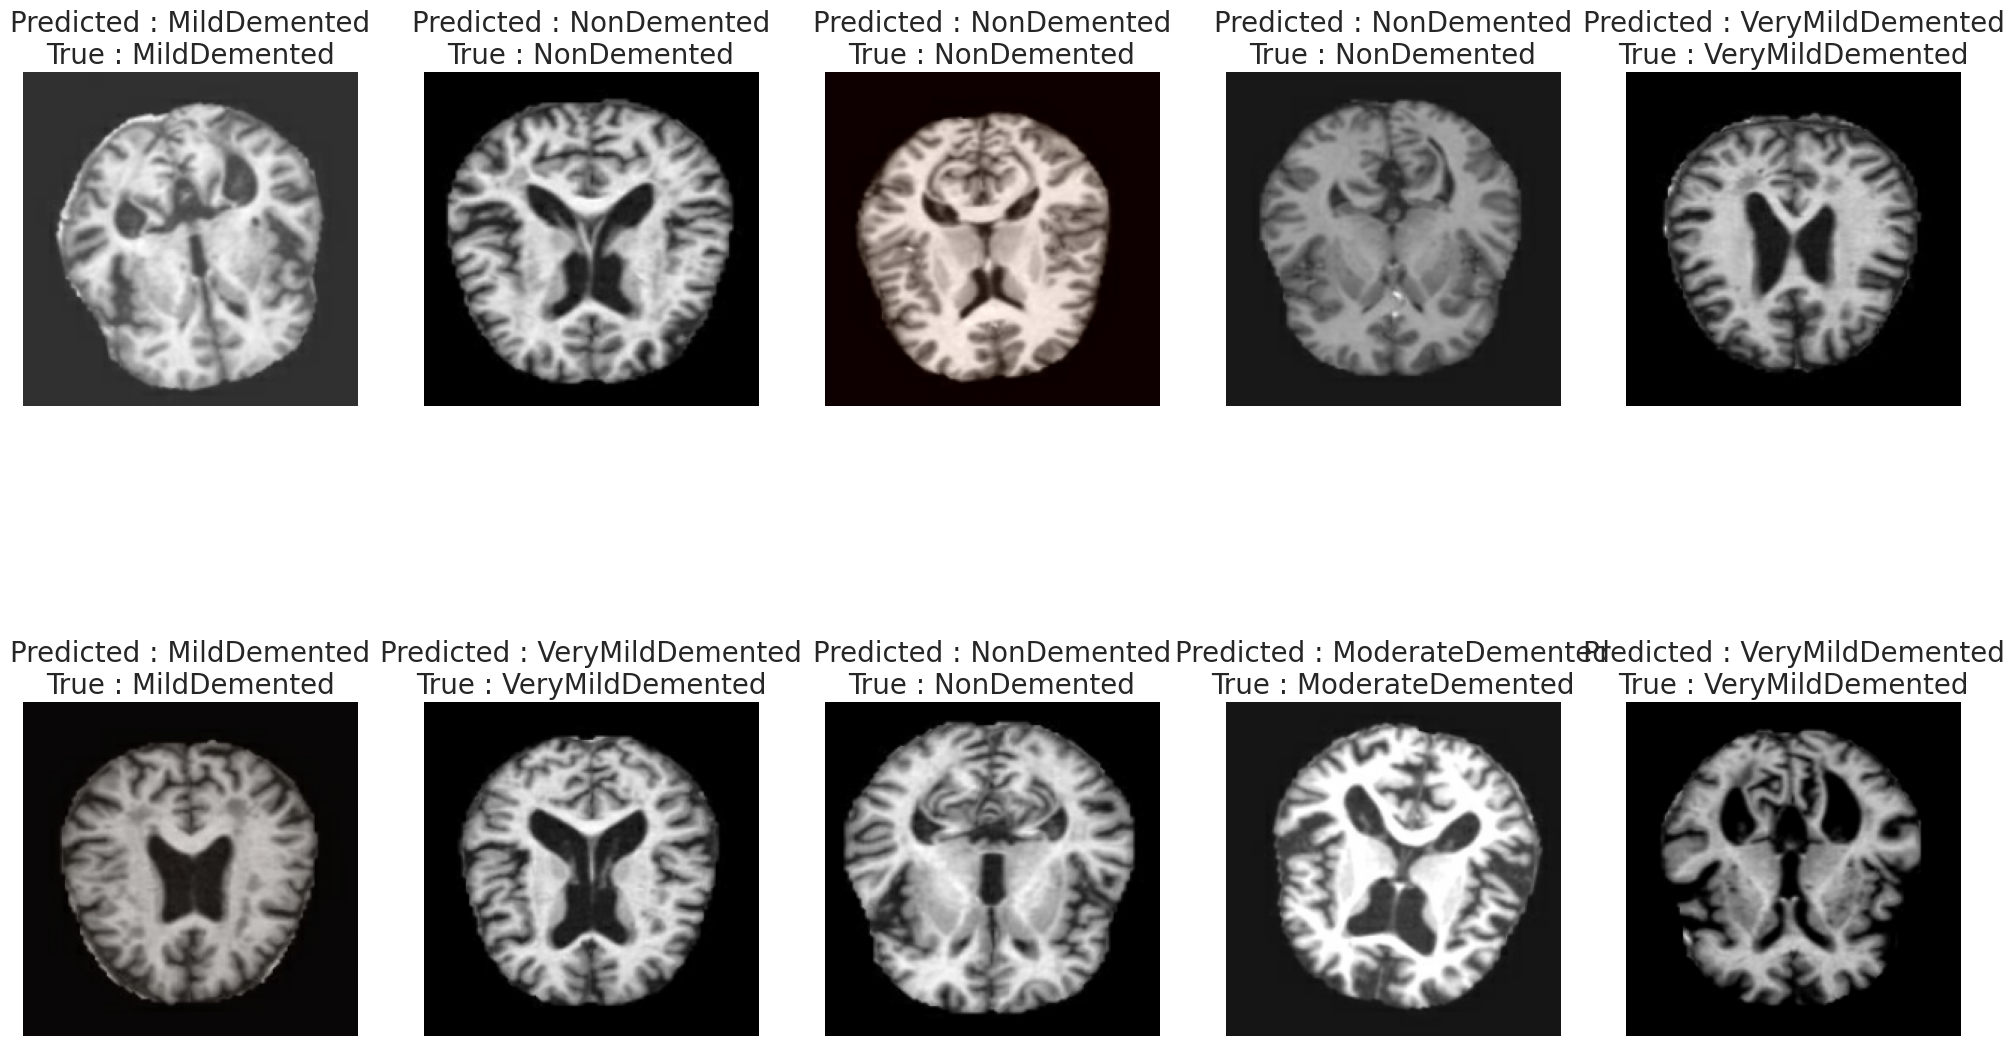

最后随机选择10个样本,展示模型的预测结果与真实标签的对比,直观了解模型在具体病例上的表现。

def predict(model, input, label):

"""

随机抽样展示模型在具体样本上的预测结果

参数:

model: 训练好的模型

input: 图像路径数组

label: 对应标签数组

# 随机选择10个不同的样本索引(不重复)

random_picks = np.random.choice(len(input), size=10, replace=False)

# 获取选中的样本

input_sample = input[random_picks]

label_sample = label[random_picks]

sample_imgs = [] # 存储处理后的图像

sample_labels = [] # 存储对应的标签

# 对每个选中的样本进行预处理

for path, label in zip(input_sample, label_sample):

img, lab = map_fn(path, label) # 使用之前定义的预处理函数

sample_imgs.append(img)

sample_labels.append(lab)

# 转换为numpy数组

sample_imgs = np.array(sample_imgs)

sample_labels = np.array(sample_labels)

# 使用模型进行预测

preds = tf.squeeze(model.predict(sample_imgs).round())

# 创建2行5列的子图网格

fig, axis = plt.subplots(2, 5, figsize=(25, 15))

# 在每个子图中显示图像和预测结果

for i, ax in enumerate(axis.flat):

ax.imshow(sample_imgs[i]) # 显示MRI图像

# 设置标题:显示预测类别和真实类别

ax.set_title(

f"Predicted : {label_map[np.array(preds[i]).argmax()]}\nTrue : {label_map[np.array(label_sample[i]).argmax()]}",

fontsize=20

)

ax.axis('off') # 关闭坐标轴

plt.show()

# 在整个数据集上执行预测可视化

predict(model, dataset_paths, dataset_labels)